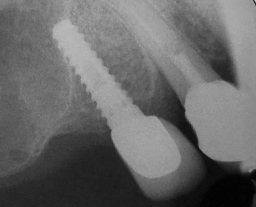

X-ray of a dental implant next to a natural tooth root.dental implants - at risk of failure?